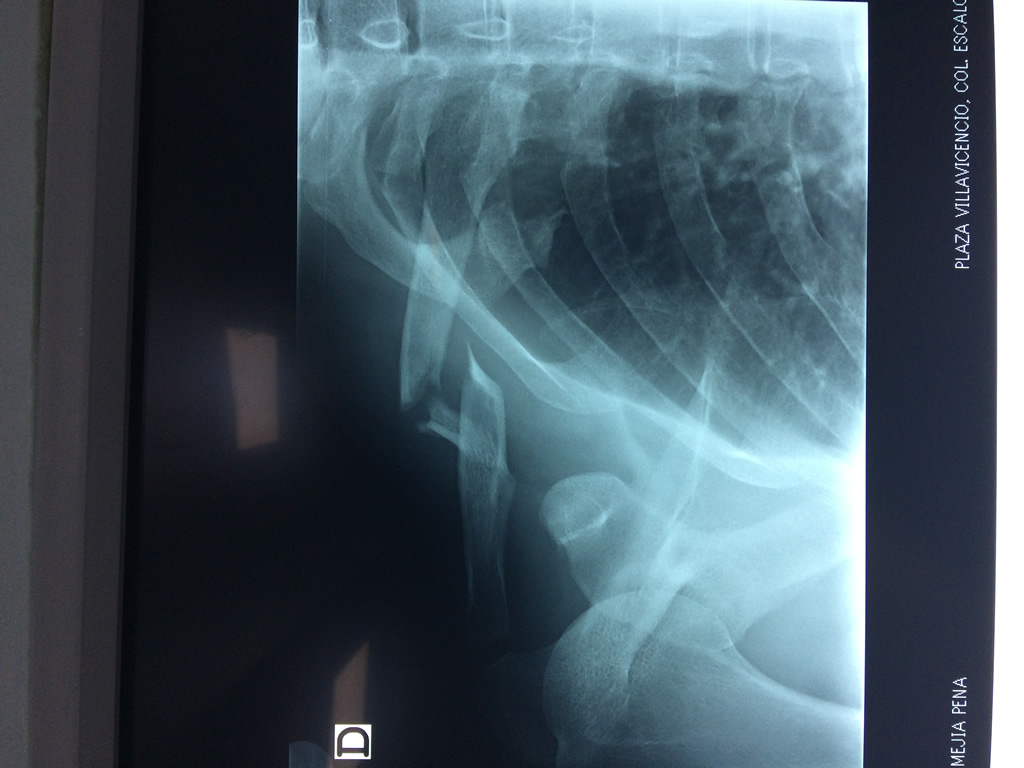

Cirugía de Fémur - Clavícula